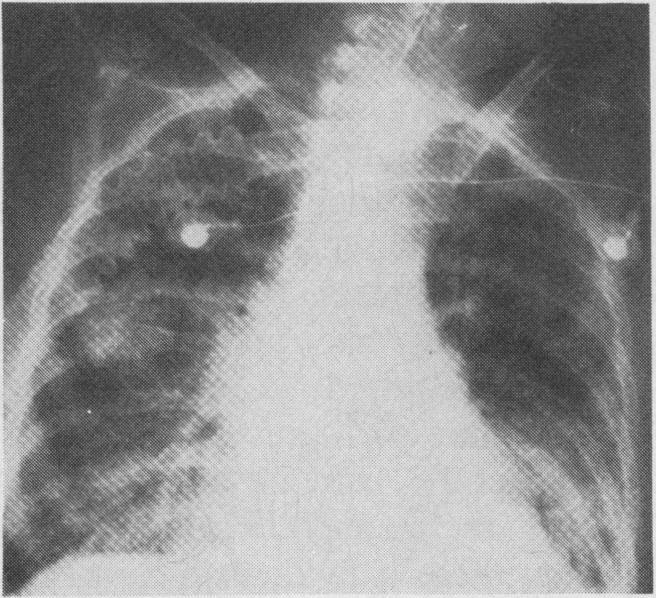

急性心肌梗死的血流动力学监测

Hemodynamic monitoring in acute myocardial infarction.

The main cause of in-hospital death in patients with acute myocardial infarction is the "power failure syndrome". Hemodynamic monitoring provides precise and current data on the filling and output status of the left ventricle and, when indicated, the right ventricle. The information obtained is used to determine the hemodynamic status more precisely than is possible from conventional clinical assessment. It permits categorization of patients by hemodynamic status; the hemodynamic subset classification of Forrester, Diamond and Swan is a powerful tool in guiding therapy and establishing prognosis in individual patients. In addition to guiding the initiation of therapy, hemodynamic monitoring is useful in the continuing assessment of potent and complex treatment. This therapy is directed at resolving hemodynamic derangements without unfavourably altering the myocardial oxygen supply-demand relationship. Specific clinical indications for hemodynamic monitoring may include confusing or complicated clinical situations in which diagnostic problems exist, complicating mechanical derangements, severe congestive heart failure, cardiogenic shock and clinical research in acute myocardial infarction.

摘要